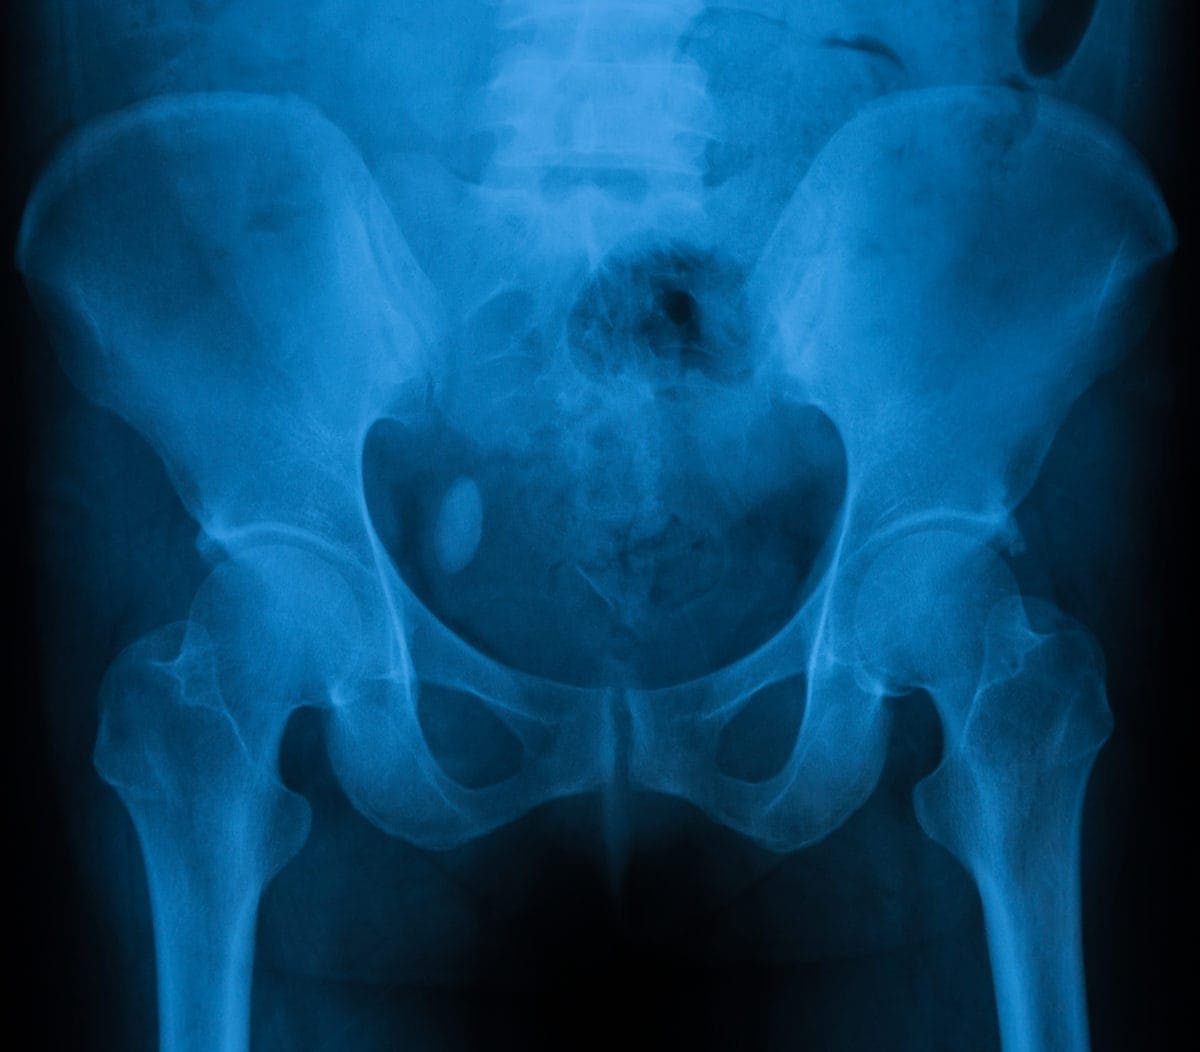

• Pelvic imaging (CT scan, X-ray, ultrasound)

• Urinary tract imaging (CT scan), which might include a special dye injected into your veins to highlights the stones